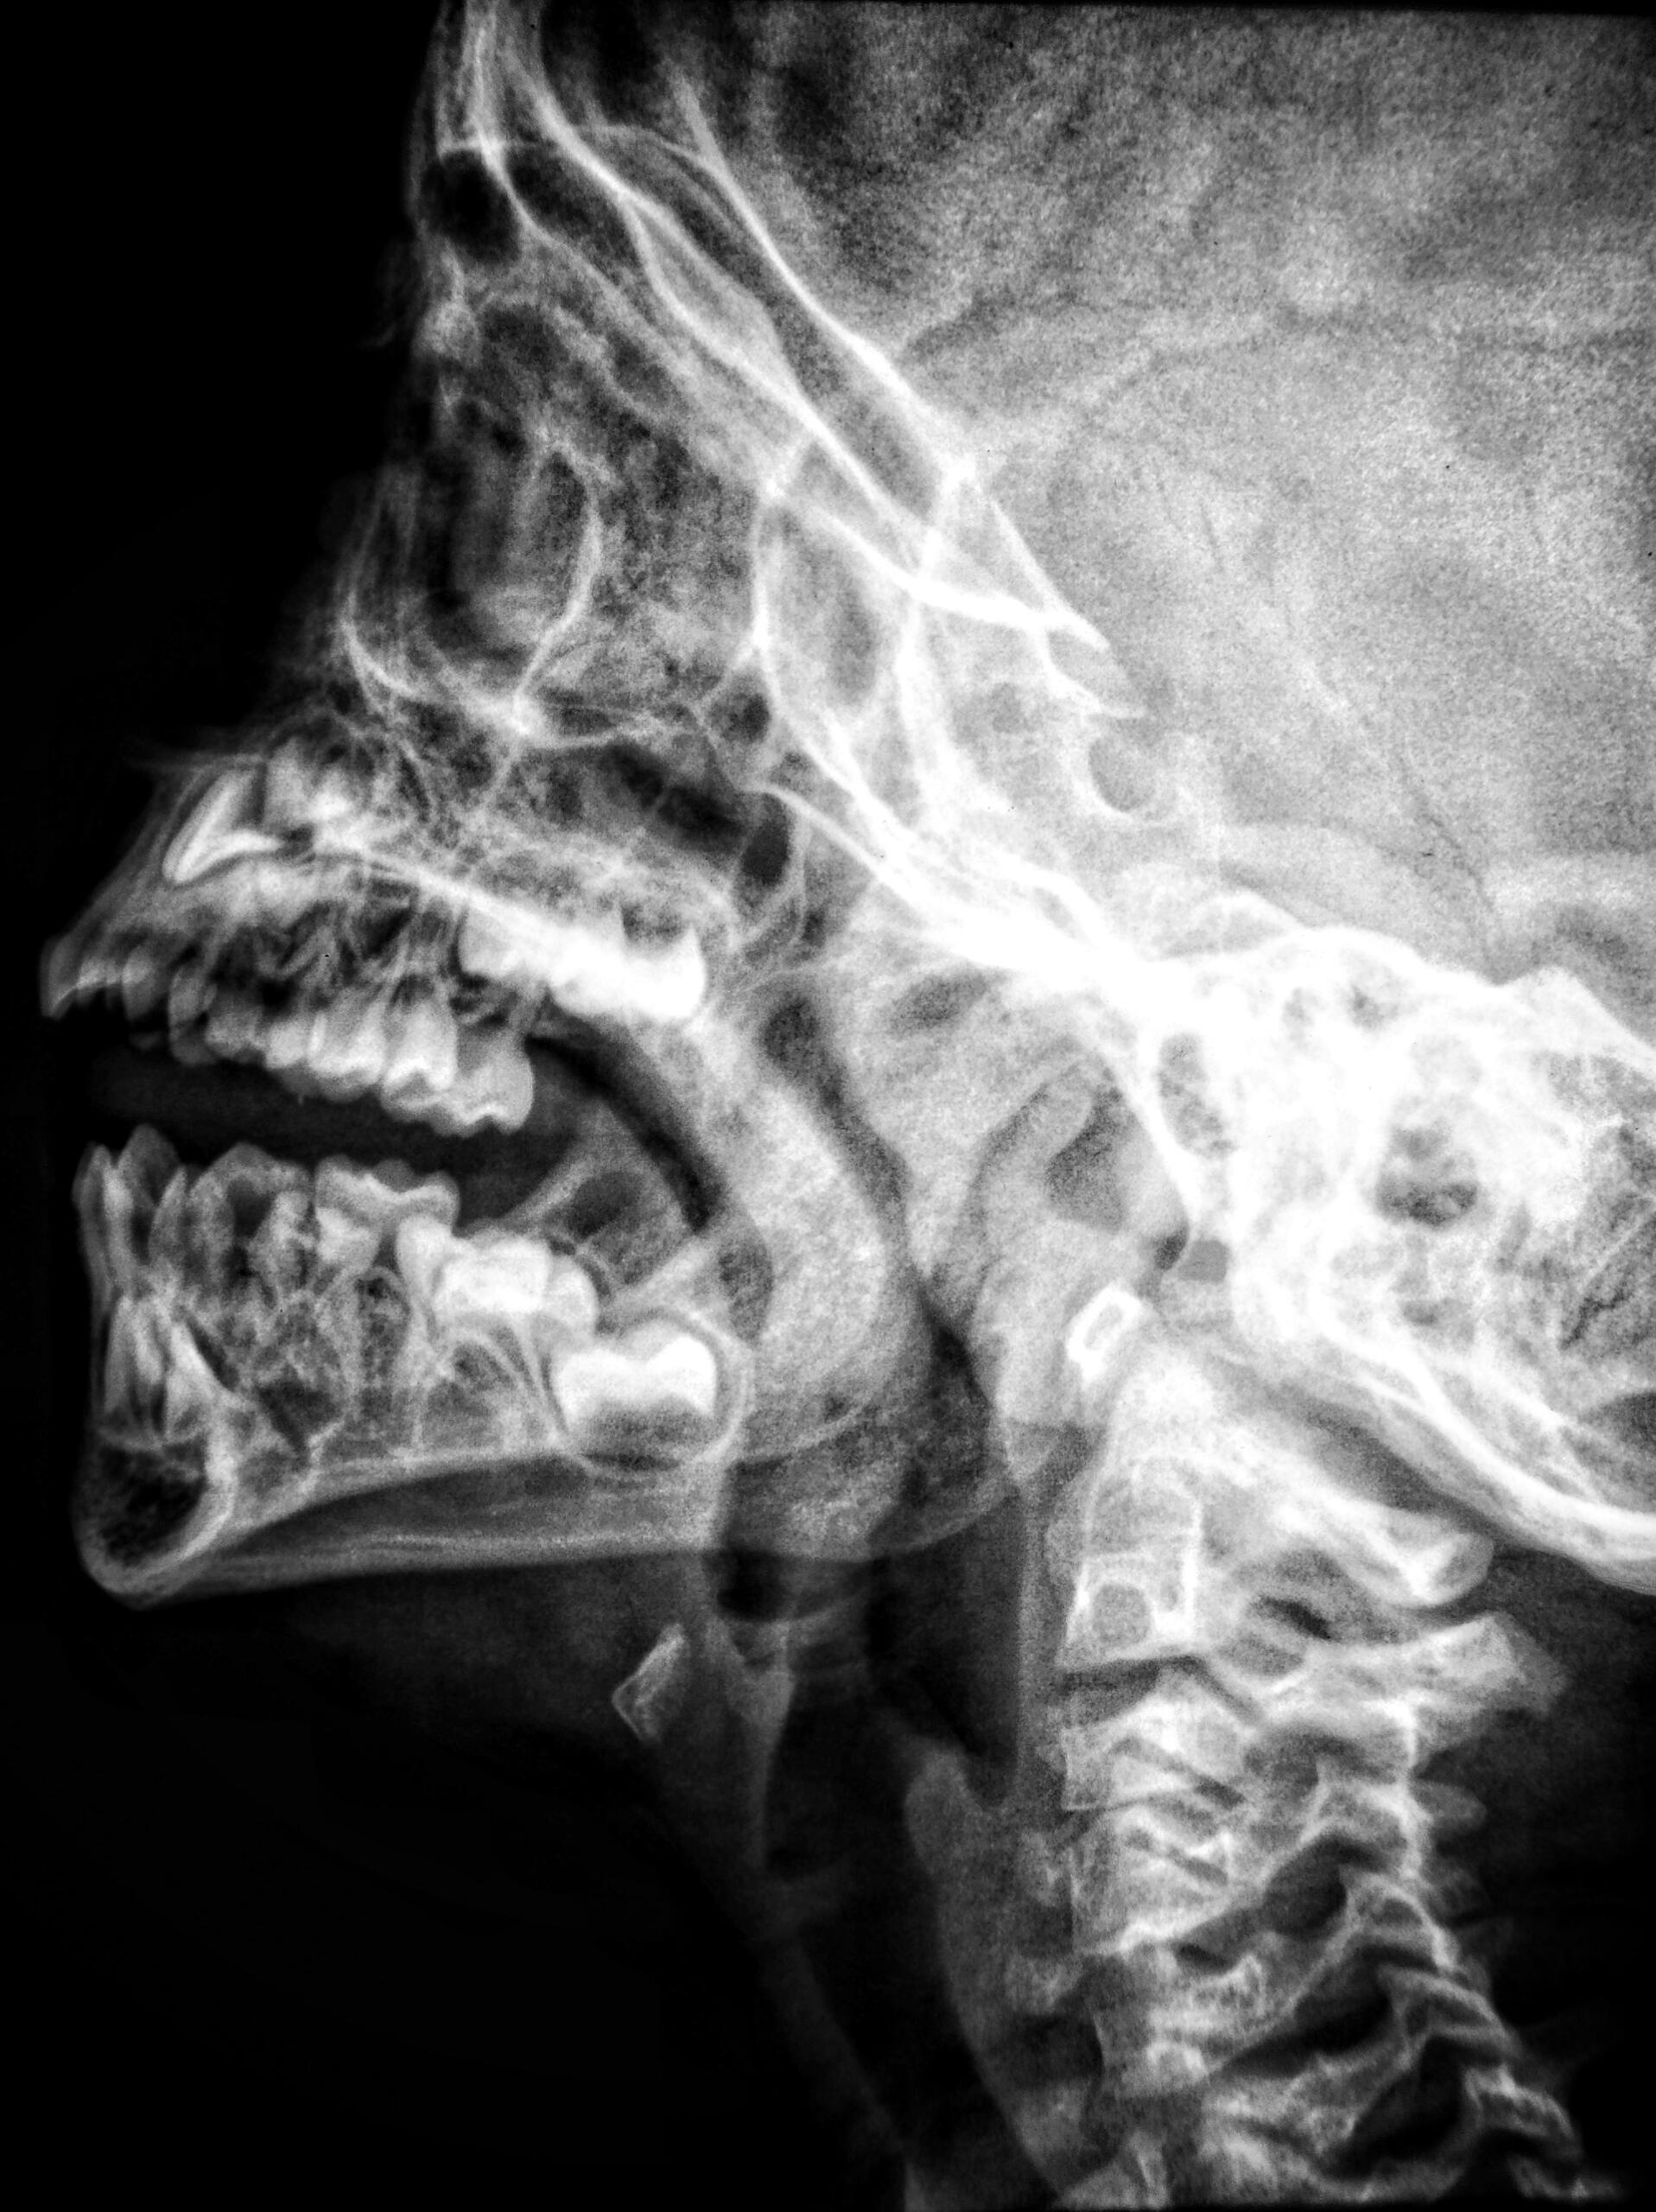

Le rayon X

Découvert par Wilhelm Röntgen en 1895

Invention n°15 : Le rayon X

Le physicien allemand Wilhelm Röntgen découvrit par hasard l'existence des rayons X. En réalité, alors qu'il étudiait les rayons cathodiques, il fit une étonnante découverte : alors qu'il travaillait avec un tube de Crookes dans lequel passait un courant électrique, et qu'il avait recouvert ce tube d'un carton noir, un autre carton recouvert d'une substance fluorescente brillait dès lors qu'il allumait le tube...

Cela signifiait donc qu'un rayonnement invisible traversait le carton noir, chose que nous pensions alors impossible. Le phénomène étant inconnu, et le rayonnement alors incompris, on l'appela donc "rayon X" !

Il entreprit des tests et découvrit, à l'aide de sa femme, que les rayons X traversaient notamment le papier, le bois et même la chair, mais pas les os ni les métaux !

Ainsi, c'était la première fois que l'humain pouvait voir son propre squelette. Cette découverte permet de visualiser l’intérieur du corps humain sans chirurgie — une révolution en diagnostic.